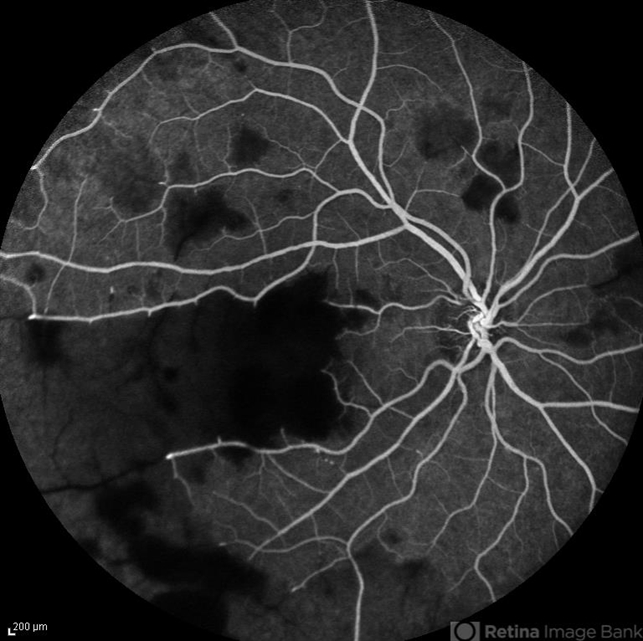

- retinal vasculitis

- Naghmeh Nozhat, Negah Eye Center, Tehran

- Imaging device

- Heidelberg Spectralis

- Early phase fluorescein angiogram of the right eye of a 28-year-old woman with acute drop of vision due to occlusive retinal vasculitis leading to extensive capillary nonperfusion and macular infarction.